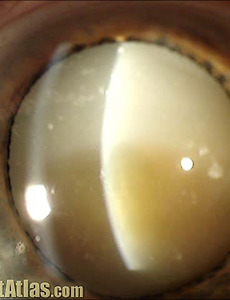

푹스홍채이색섬모체염, 푹스홍채이색모양체염(Fuchs Heterochromic Iridocylitis, FHIC) 푹스홍채이색섬모체염 순수우리말로 표현하자면.. 푹스홍채이색모양체염이라 불리는.. Fuchs Heterochromic Iridocylitis, FHIC 는.. 문자그대로, 홍채의 이색증(홍채의 색깔이 다름, 눈동자 색깔이 다름)을 특징으로 하는, 만성적인 단안의 홍채섬모체염입니다. 즉, 만성적으로 한쪽눈에서 앞포도막염이 발생하는데, 이로 인해서 양안의 홍채의 색깔이 다름(홍채이색증)이 특징적인 질환으로, 안과의사 푹스(Fuchs)에 의해서 밝혀진 질환입니다. ① 홍채의 이색증 (Heterochromic Iris) 양안 눈동자의 색깔이 다르다는것이 전형적인 특징인데, 햇빛처럼 분산되는 백색광하에서 양안의 색깔을 비교해보면, 양안에 미묘한 색깔 다름이 관찰됩니다 이는 홍채의 기질 위축에 의해서 발생하는 것으로.. 2018. 4. 8.